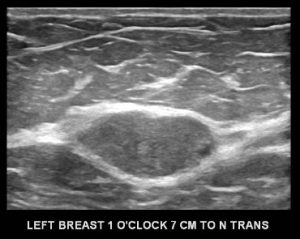

The ultrasound of the expected position of the mass is performed. A representative image:

What is your assessment and recommendation?

D. BI-RADS 3 (Probably Benign); Six month follow-up

Explanation: This non-palpable, solid, circumscribed oval mass can be assessed as “Probably Benign”, meaning that it has a less than a 2% chance of being malignant. The assessment of BI-RADS 3 can be given with a recommendation for short term follow-up (diagnostic ultrasound in six months). Once two years of stability has been documented for this mass, it can finally be designated benign with no specific follow-up needed.

As per the ACR BI-RADS manual 5th edition, there are three mammographic findings which can be designated as BI-RADS 3, Probably Benign:

- A solid mass which is non-palpable, non-calcified, circumscribed, oval or round (as seen in this case).